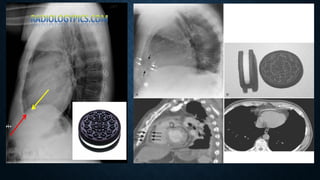

HEMOPERICARDIUM

• Hemopericardium refers to the presence of blood within the pericardial cavity. Can occur

from blunt/penetrating/deceleration trauma.

• Plain radiograph

• enlargement of the cardiac silhouette may be present but chest x-rays are insensitive and

non-specific.

• the "straight left heart border" is an infrequent sign with low sensitivity (~40%) for

hemopericardium in penetrating trauma patients.

• ​

the Oreo cookie sign on lateral CXR.